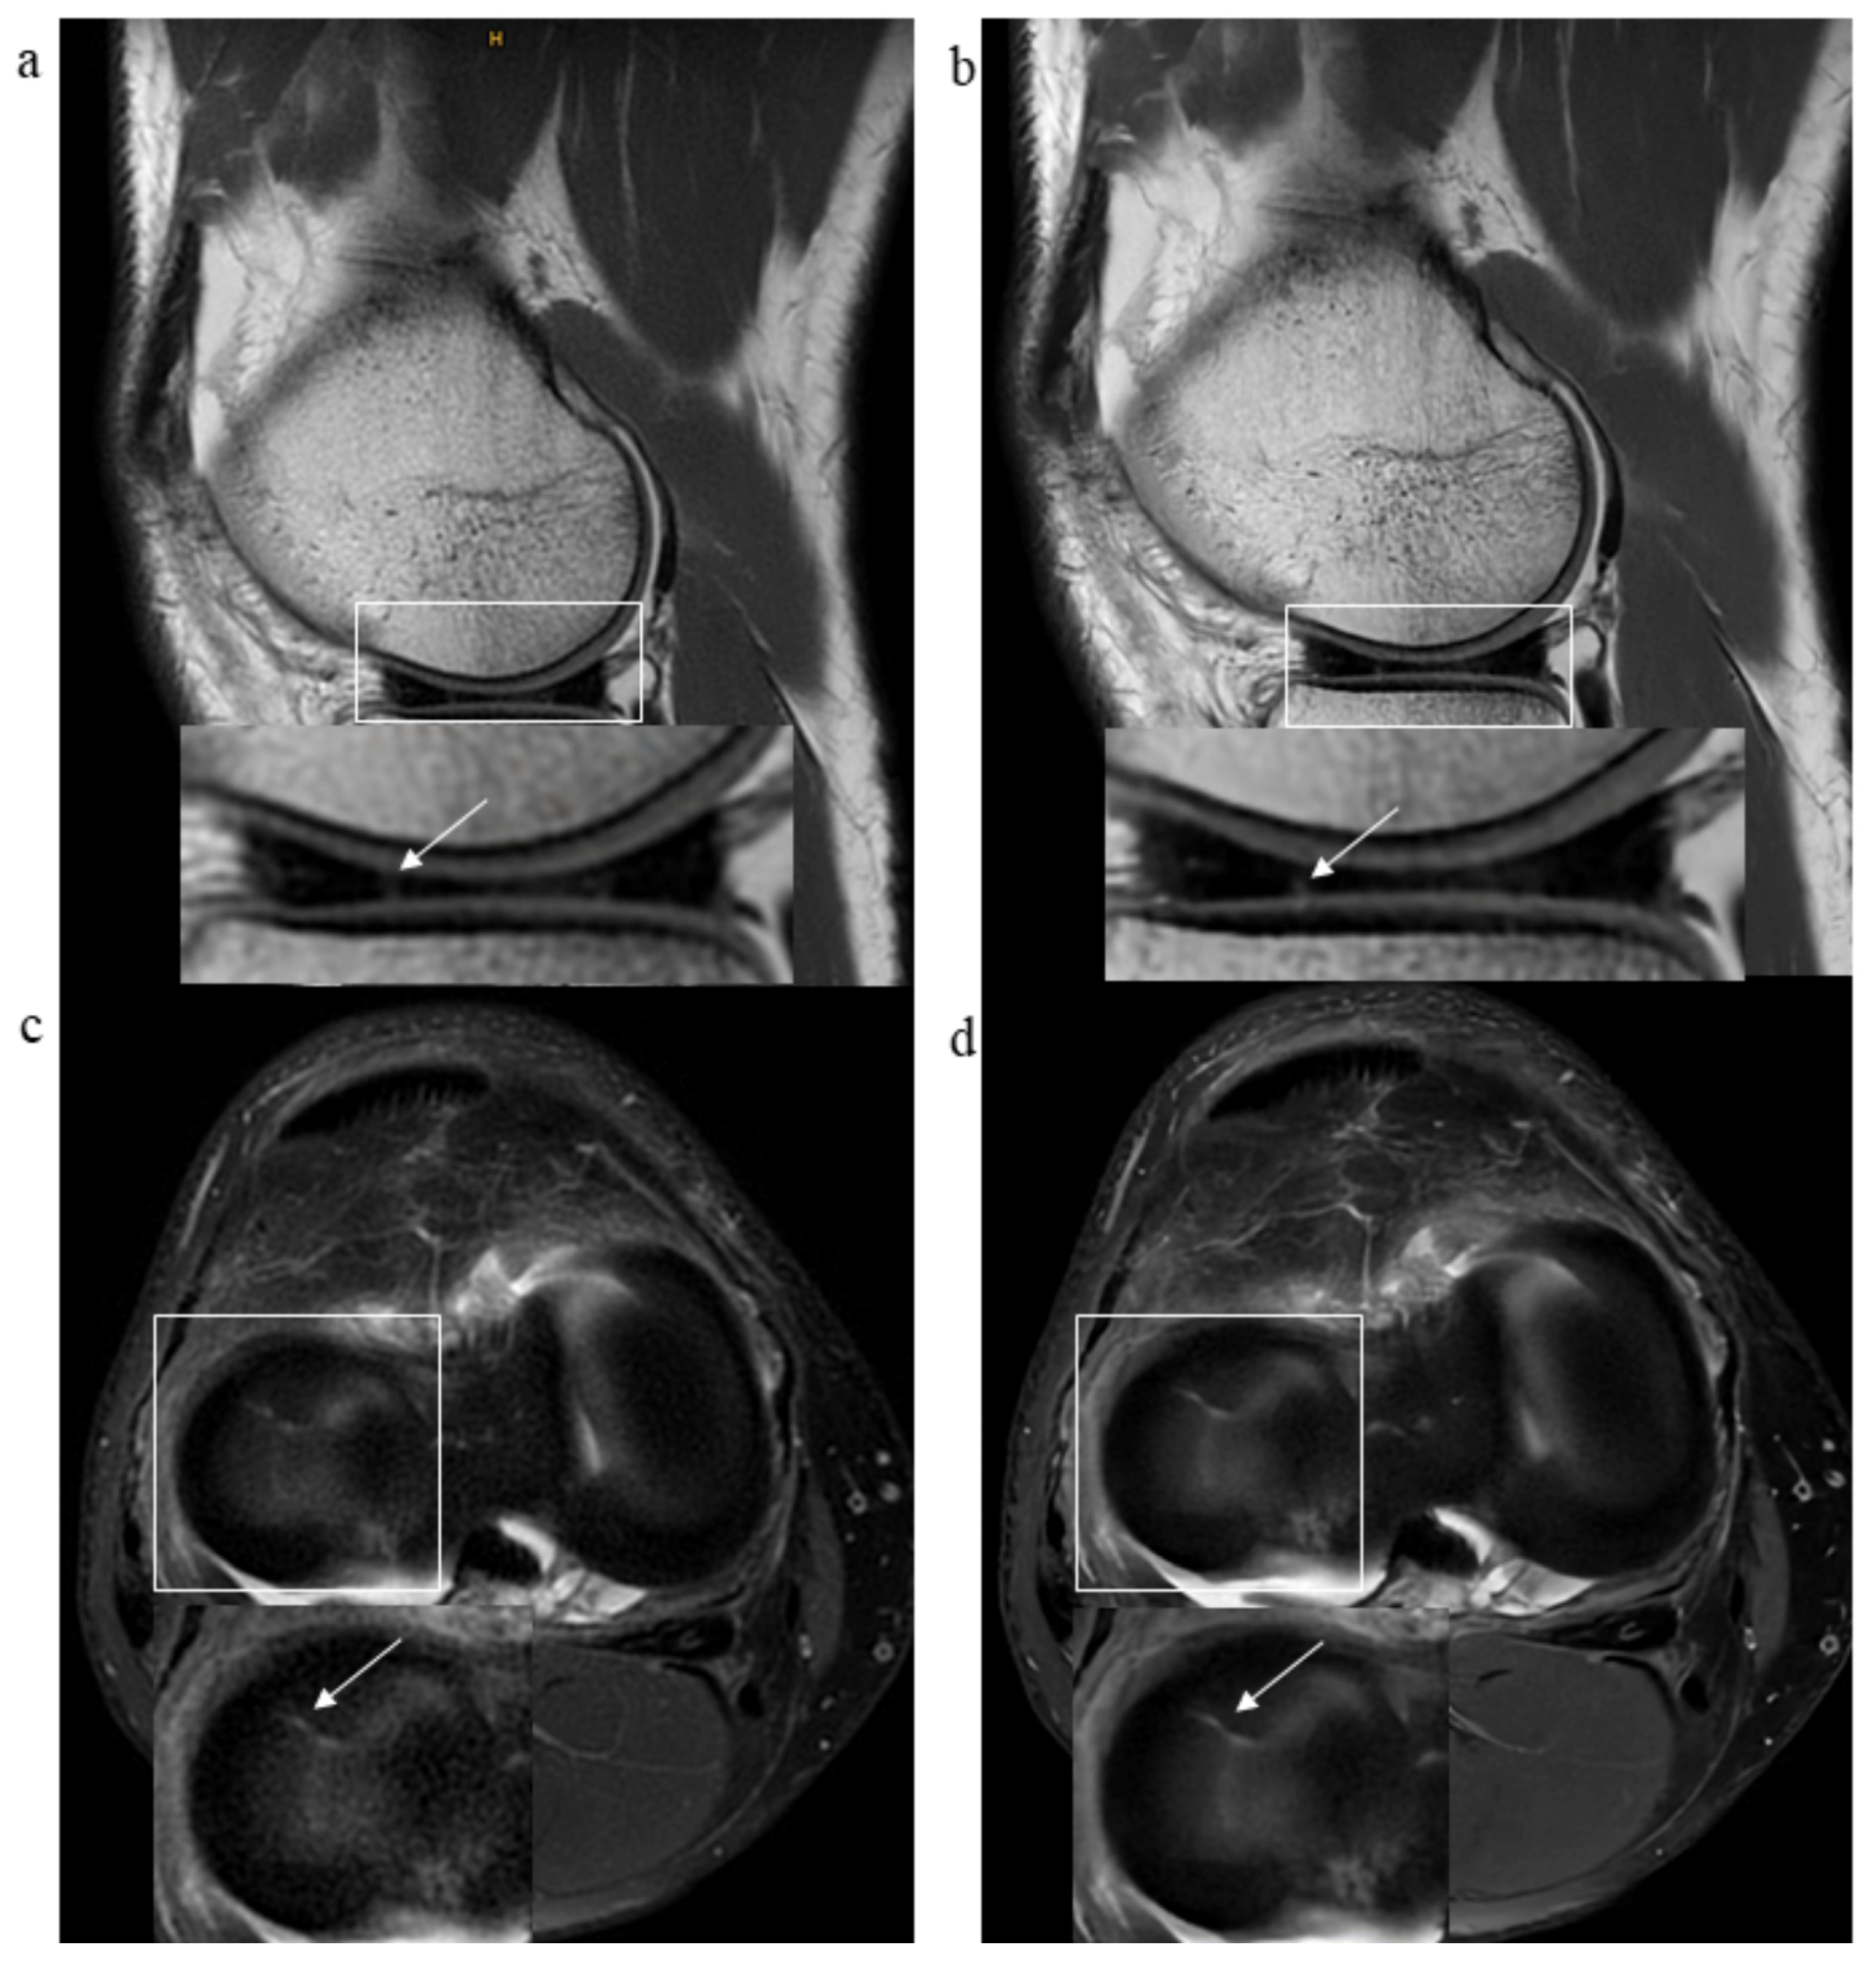

3.2. Pathological Findings

3.3. Signal-to-Noise and Contrast-to-Noise Ratios